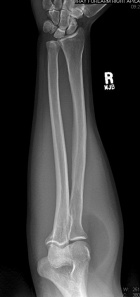

46 year old male with painless forearm mass

Zoom image: Radiological image Radiological image.